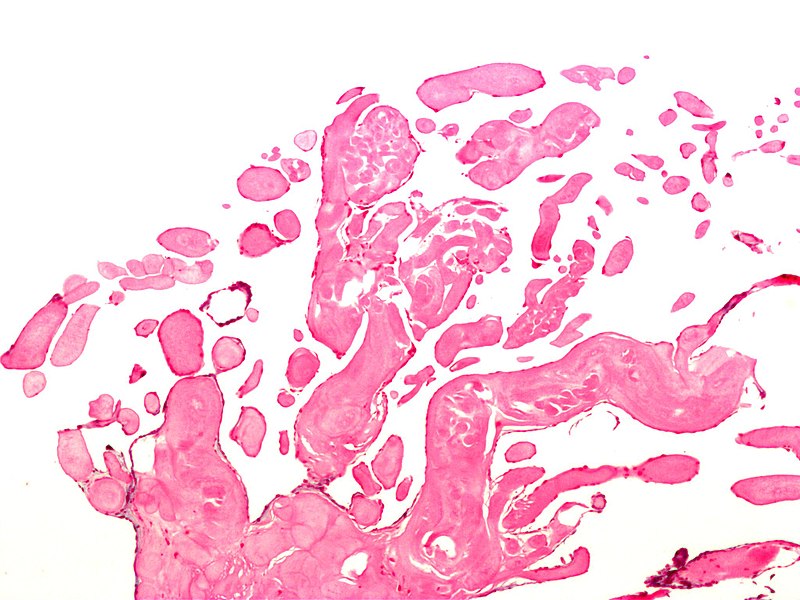

Rhabdomyomas are benign hamartomas of cardiac muscle.

Rhabdomyomas normally arises in the ventricle.